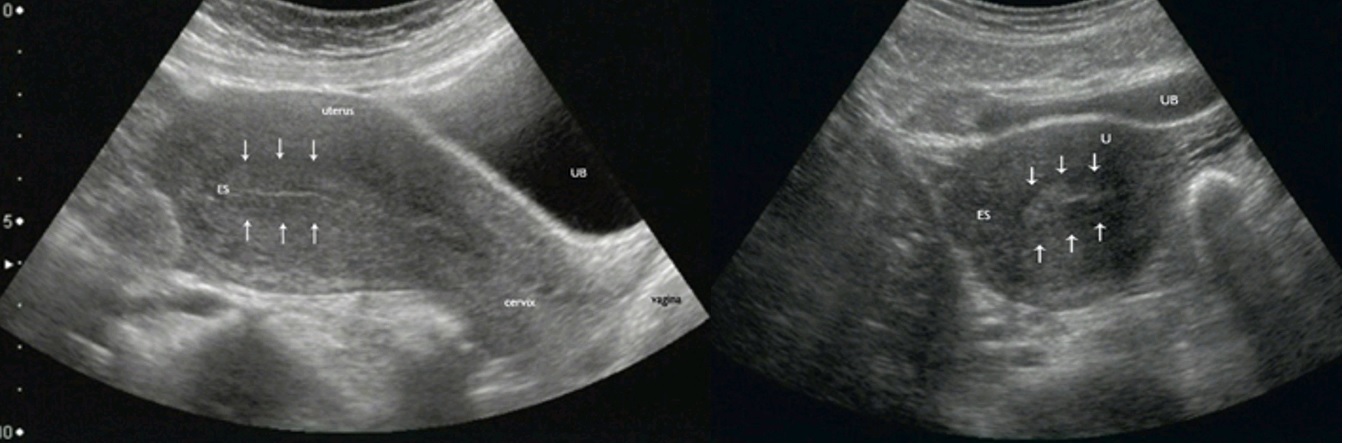

In women, pelvic ultrasound is most often used to evaluate the uterus, cervix, ovaries, fallopian tubes (uterine tubes), and bladder.

Transvaginal ultrasound is typically used to view the endometrium (lining of the uterus) and ovaries. Transvaginal ultrasound also evaluates the myometrium (muscle walls of the uterus). These exams are often performed to detect the following: